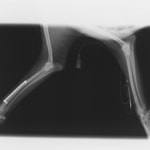

ペルシャ猫 11ヶ月齢 雄

他院にて左大腿骨遠位の成長板骨折(salter-harrisⅠ型)が認められており、治療相談を目的として来院。当院にて、キルシュナーワイヤーを用いたピンニングにより骨折部位の整復を行いました。術後の経過は良好で、現在も経過観察中です。

術前レントゲン

術後レントゲン

機器

Arthrex社のターゲティングデバイスを用いてピンニングの位置を調整することで、確実な固定を行っています。当院ではこの手術器具以外にも、人の手術にも使用される様々な器具を導入し、手術精度を高め、また医療メーカーと新しい器具の開発、試作にも取り組んでおります。